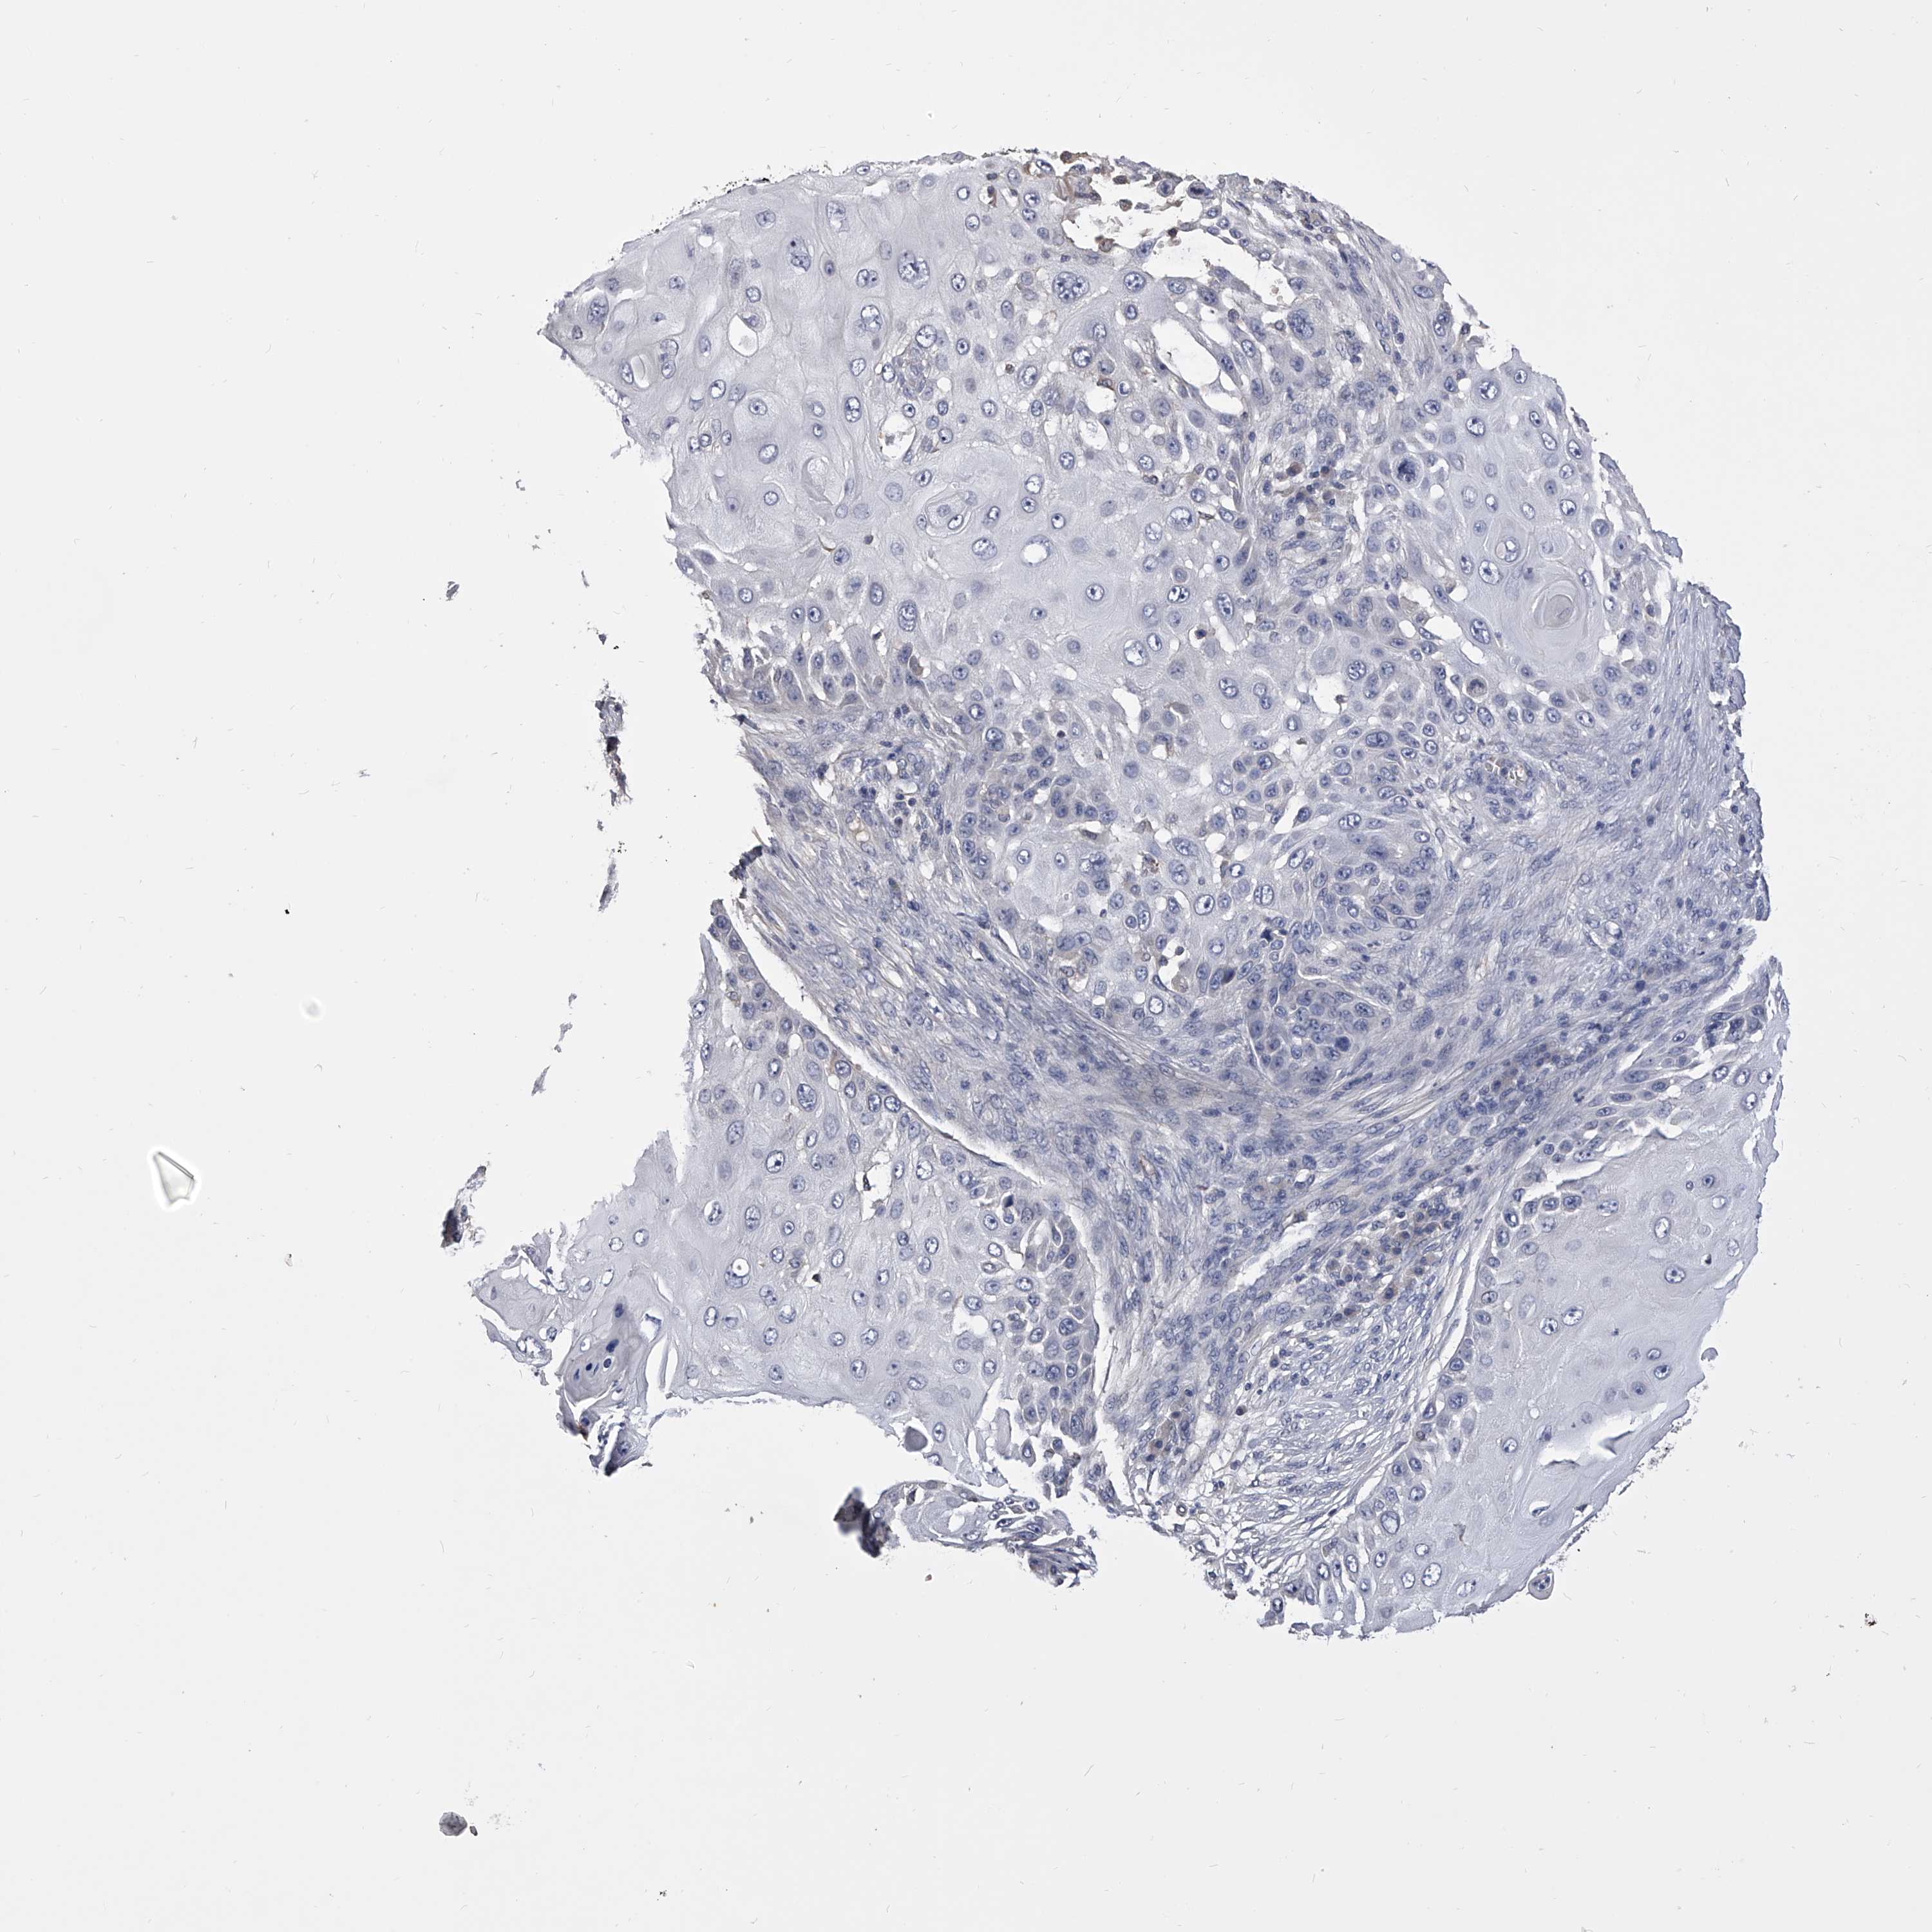

SKIN CANCER - Protein expressioni

A mouse-over function shows sample information and annotation data. Click on an image to view it in a full screen mode. Samples can be filtered based on level of antibody staining by selecting one or several of the following categories: high, medium, low and not detected. The assay and annotation is described here.

Each image is clickable and will lead to virtual microscopy that enables deeper exploration of all samples and also displays staining intensity scores, fraction scores and subcellular localization as well as patient and tissue information for each sample.

Antibody HPA029666

Antibody HPA029667

Antibody HPA029668

Antibody HPA029669

Basal cell carcinoma

Squamous cell carcinoma, NOS

Squamous cell carcinoma, metastatic, NOS